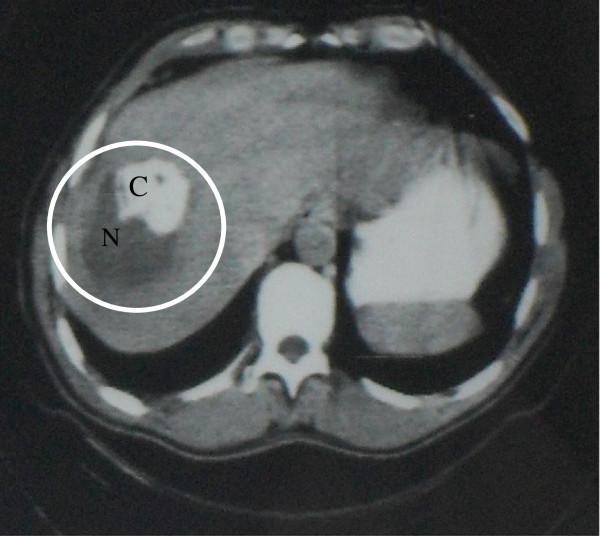

We report the 30-yr history of a well-documented human case of alveolar echinococcosis, with a lung lesion at presentation followed by the discovery of a liver lesion, both removed by surgery. Subsequently, within the 13 years following diagnosis, metastases were disclosed in eye, brain and skull, as well as additional lung lesions. This patient had no immune suppression, and did not have the genetic background known to predispose to severe alveolar echinococcosis; it may thus be hypothesized that iterative multi-organ involvement was mostly due to the poor adherence to benzimidazole treatment for the first decade after diagnosis. Conversely, after a new alveolar echinococcosis recurrence was found in the right lung in 1994, the patient accepted to take albendazole continuously at the right dosage. After serology became negative and a fluoro-deoxy-glucose-Positron Emission Tomography performed in 2005 showed a total regression of the lesions in all organs, albendazole treatment could be definitively withdrawn. In 2011, the fluoro-deoxy-glucose-Positron Emission Tomography showed a total absence of parasitic metabolic activity and the patient had no clinical symptoms related to alveolar echinococcosis.The history of this patient suggests that multi-organ involvement and alveolar echinococcosis recurrence over time may occur in non-immune suppressed patients despite an apparently "radical" surgery. Metastatic dissemination might be favored by a poor adherence to chemotherapy. Combined surgery and continuous administration of albendazole at high dosage may allow alveolar echinococcosis patients to survive more than 30 years after diagnosis despite multi-organ involvement.